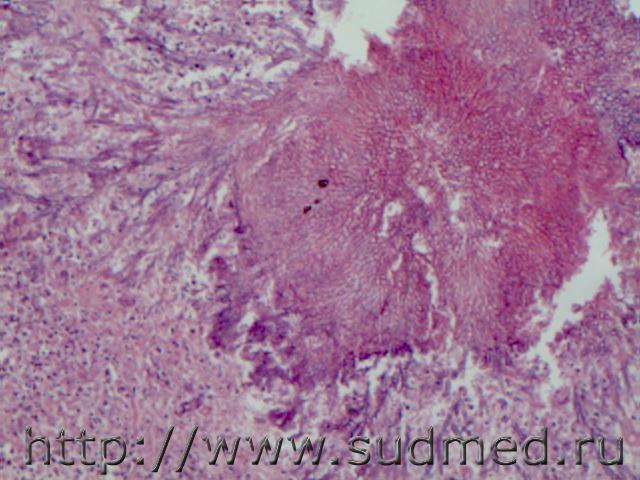

Эпидермоидный рак легких с метастазами л/у и в миокард( центральным ороговением,стратификацией, базальноклеточная ориентация, плоские клетки с межклеточными мостиками)